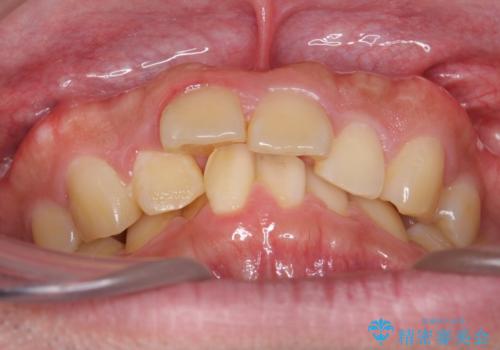

- 前歯の前突を主訴に来院。

上の歯並びが前方にずれていました。

上顎は歯を抜かずに、奥歯を後ろに下げる治療を行っています。

下顎は歯列を拡大して並べました。

矯正前に下顎の骨隆起の切除をご希望により行っています。(Dr.大元執刀)

歯を抜かずに奥歯を後ろに動かすために、矯正用のミニスクリューを使用しています。

また、過蓋咬合(深いかみ合わせ)で食いしばりがきつく、歯の移動には大変時間がかかりました。